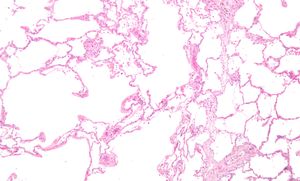

الپاثولوجيا العيانية للرئة تظهر انتفاخ الرئة المركزي بسبب التدخين.

صورة مجهرية تظهر نفاخ الرئة (على اليسار - مساحات فارغة كبيرة) ونسيج الرئة مع محافظة نسبية على الحويصلات الهوائية (على اليمين).